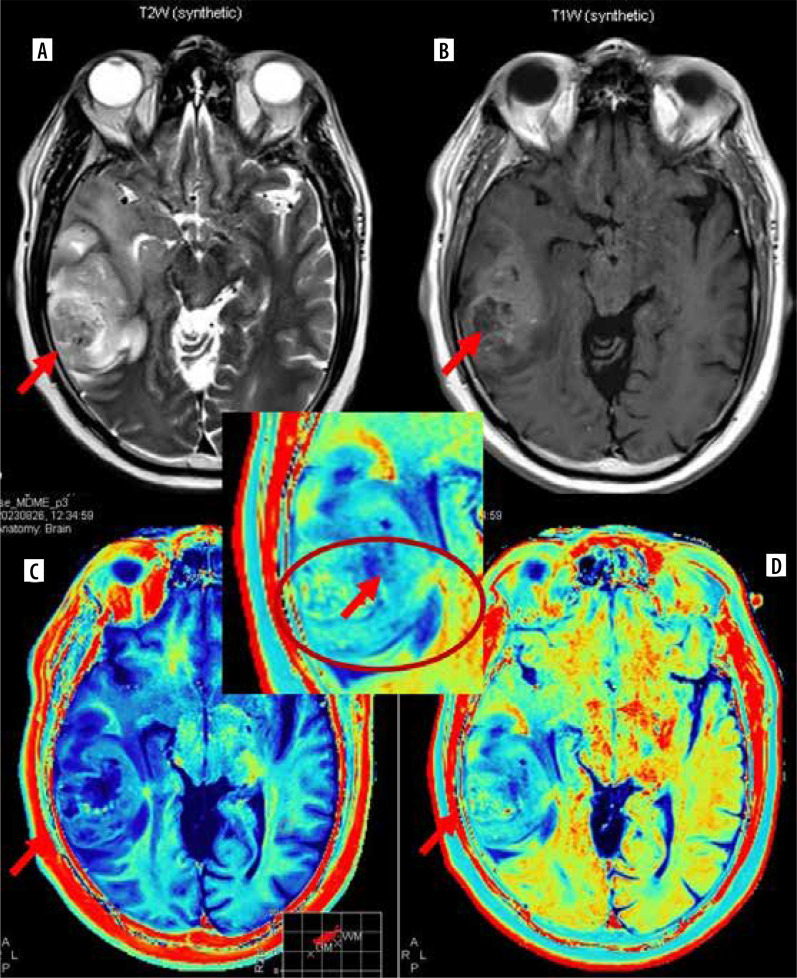

Purpose: Synthetic magnetic resonance imaging (MRI) allows reconstruction of multiple contrast-weighted images from a single acquisition of multiple delay multiple echo (MDME) sequence with quantitative relaxometry (longitudinal relaxation rate [R1], transverse relaxation rate [R2], and proton density [PD]) in a shorter acquisition time. We tried to explore synthetic MR-based relaxometry to differentiate central nervous system (CNS) tuberculomas from primary CNS neoplasm like glioblastoma.

Material and methods: Ten cases of CNS tuberculoma and 14 cases of glioblastoma underwent pre- and post-contrast synthetic MRI. R1, R2, and PD values were calculated from lesion core, wall, and perilesional oedema using free-hand region of interest and compared across the 2 groups.

Results: Both pre- and post-contrast R1 and R2 relaxation rates from core were significantly higher in tuberculoma (mean pre-contrast R1 - 0.93, R2 - 15.02; post-contrast R1 - 1.51, R2 - 15.48) from glioblastoma (mean pre-contrast R1 - 0.36, R2 - 4.58; post-contrast R1 - 0.43, R2 - 4.78). The same values were higher in perilesional oedema of glioblastoma (mean pre-contrast R1 - 0.75, R2 - 9.9; post-contrast R1 - 0.78, R2 - 10.48) compared to tuberculoma (mean pre-contrast R1 - 0.68, R2 - 8.57; post-contrast R1 - 0.72, R2 - 8.67). No significant difference was seen between relaxometry parameters from the walls of lesions.

Conclusions: Synthetic MR-based relaxometry can be useful in distinguishing CNS tuberculomas from glioblastoma. R1 and R2 relaxation rates from core of the lesions are most important in differentiating the two with R1 value > 0.852 and R2 value > 11.565 from core strongly suggests tuberculoma over glioblastoma.